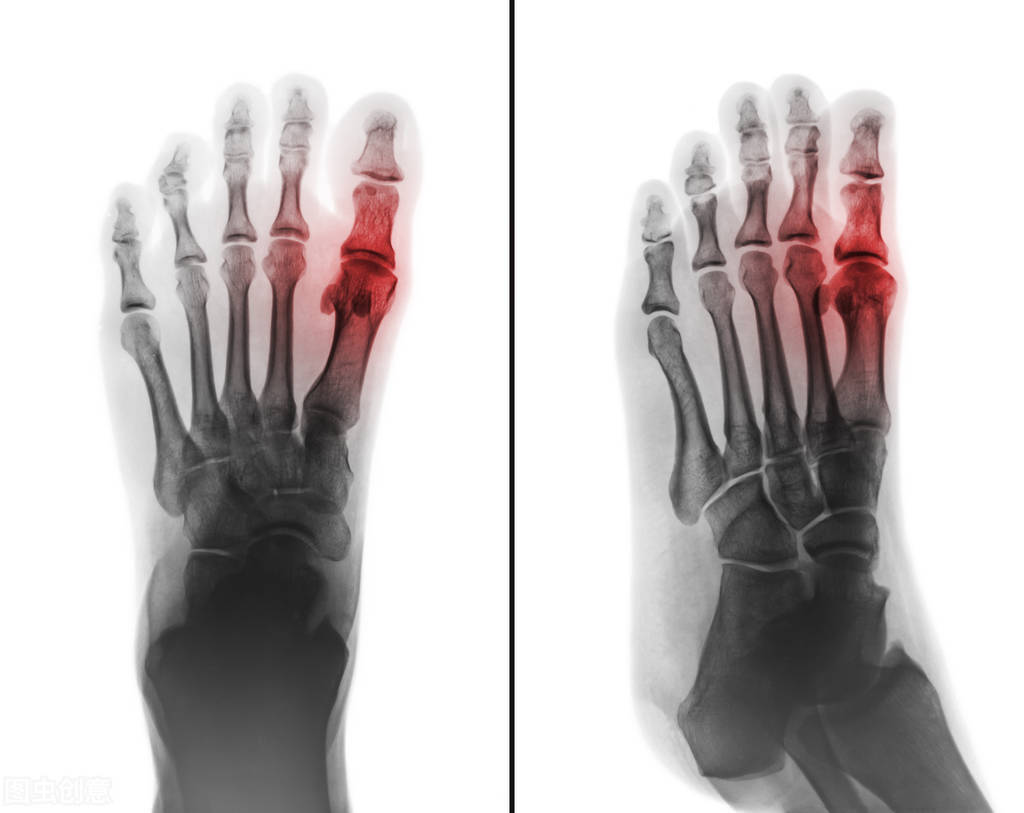

非布司他的药品说明书中,适应症一项仅仅推荐了痛风患者高尿酸血症的长期治疗,不推荐用于无症状高尿酸血症患者。这是因为,非布司他通过抑制黄嘌呤氧化酶来抑制尿酸合成,从源头上阻断血清尿酸来源,因此具有强大的降尿酸作用。但是对于无症状高尿酸血症患者来说,尿酸水平的升高与高嘌呤饮食的摄入,酗酒,肥胖等代谢因素密切相关。是一种生活方式病,需要通过严格自律的健康生活方式调整来控制,服用药物虽然可以在短期内降低尿酸水平,但长期服用降尿酸药物的安全性还需要获益与风险的权衡,此外,虽然尿酸水平升高会增加心血管疾病发生风险,但是尿酸水平降低是否会降低心血管疾病发生风险尚没有临床证据来证实,对于患者来说,对于长期服药降尿酸的安全性的担忧和依从性也是需要临床考虑的问题。也正因为如此,最新的美国痛风指南不推荐对于无症状高尿酸血症患者进行药物降尿酸治疗,而亚洲指南多持有积极态度,并认为对于无症状高尿酸血症患者积极降尿酸治疗能有更多的临床获益尤其心血管方面的获益,因为高尿酸血症不仅仅会诱发痛风,还会增加糖尿病,冠心病等疾病的发生风险。而对于痛风患者来说,由于已经出现了尿酸盐结晶形成,并且对关节肾脏造成了不同程度的损害,因此降尿酸治疗对于减少痛风急性发作次数,避免痛风对关节,肾脏以及心血管系统的进一步损害有着更加积极的意义,获益大于风险,在无症状高尿酸血症降尿酸治疗方案中,中国指南推荐的一线药物是苯溴马隆和别嘌醇,并没有推荐非布司他,更多的考虑是基于非布司他原研产品的说明书和心血管安全性问题